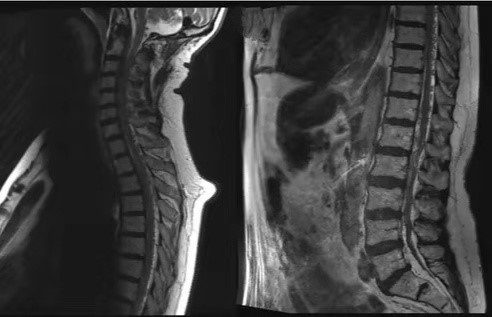

2日后,患者携带片子找苏灿复诊,苏灿定睛一看,发现患者的脊髓MRI有典型的虫蚀样血管流空影(见下图)。

这是典型的脊髓硬脊膜动静脉瘘的影像学表现,苏灿将其收住院,并安排介入科医生会诊,预约行脊髓血管造影

和栓塞治疗。